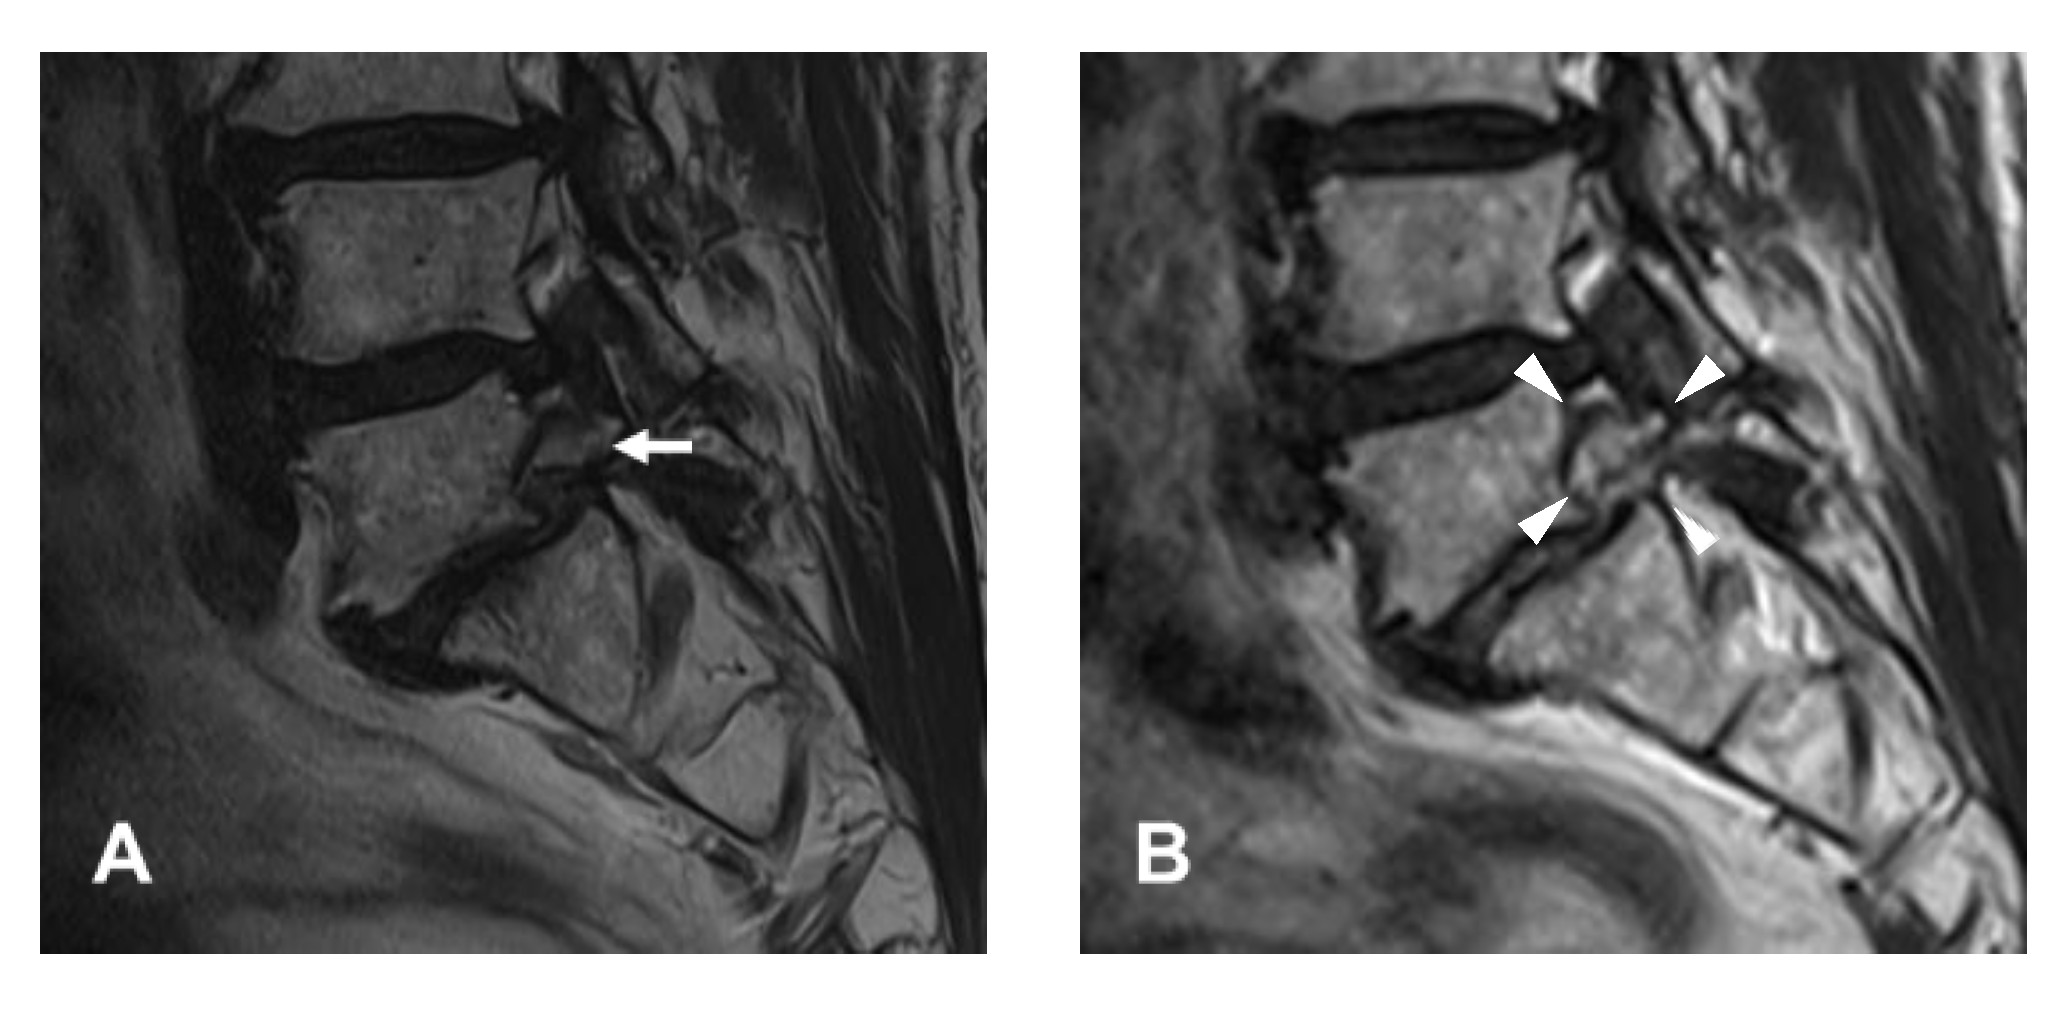

2.1. Patient Evaluation

4.1. Diagnosis and Clinical Outcomes